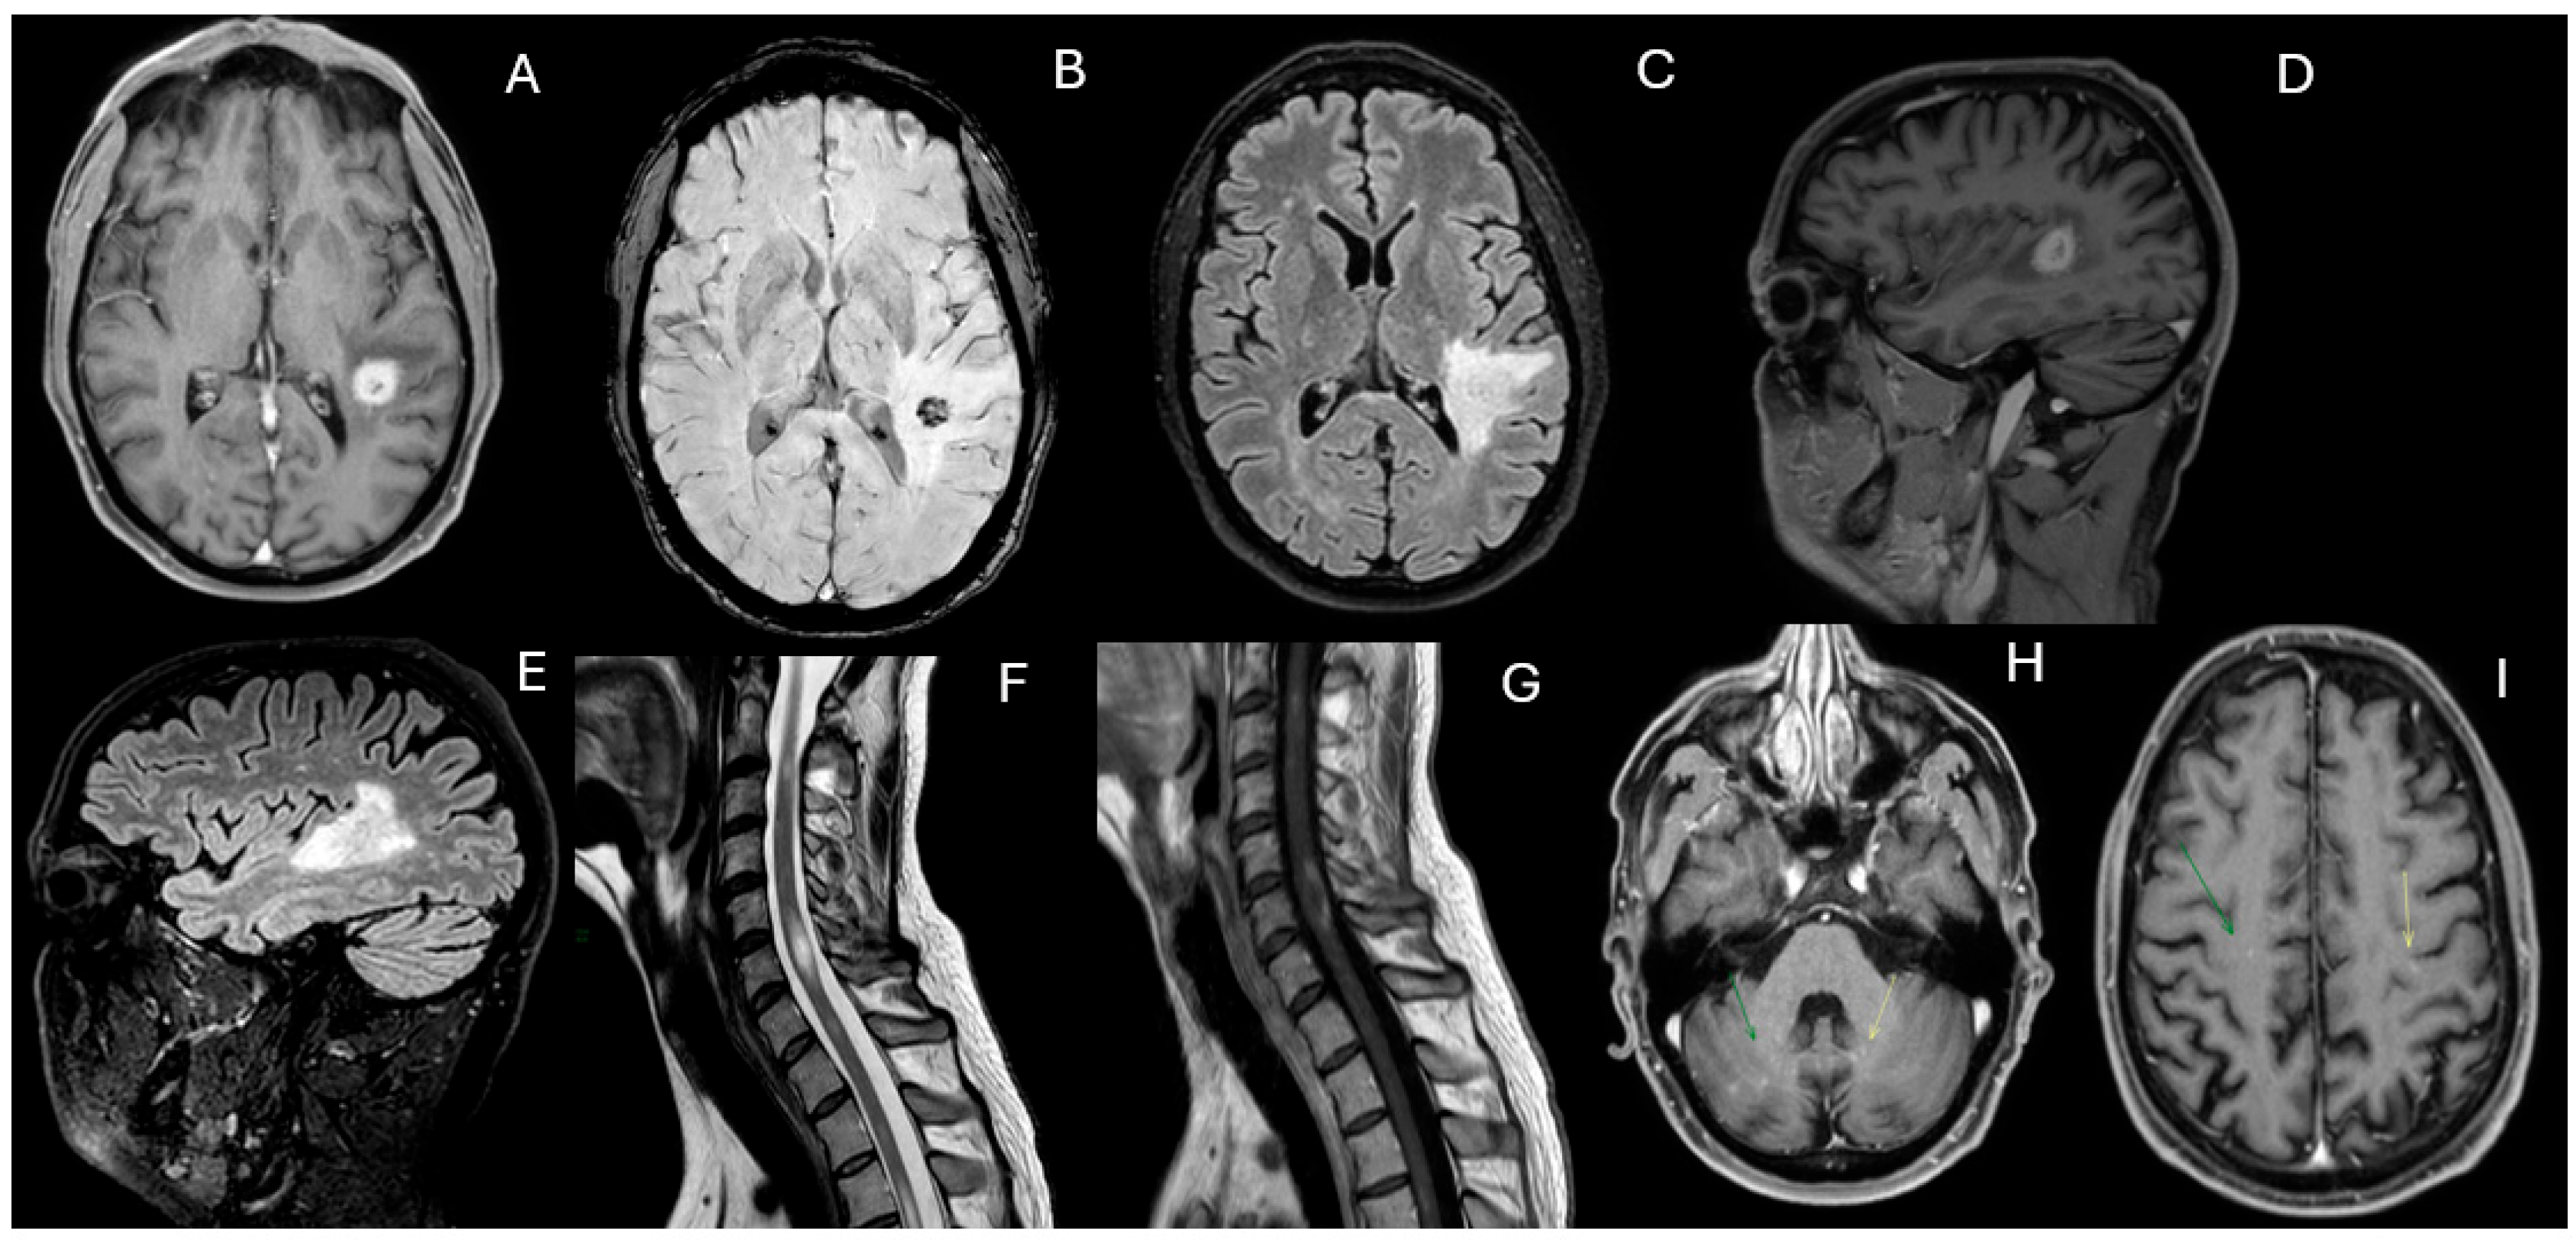

However, in February 2023, cyclophosphamide was discontinued due to liver toxicity, and mycophenolate mofetil (2 g daily) was initiated. By May 2023, worsening neurological symptoms consisting of gait disturbances and a left-sided sensorimotor hemisyndrome prompted an additional MRI, which demonstrated extensive new FLAIR hyperintense and contrast-enhancing lesions in the deep white matter and spinal cord (Figure 3). Limited response to intravenous methylprednisolone (1 g daily for five days) led to five sessions of plasmapheresis, which significantly improved clinical symptoms. Treatment with rituximab (1 g on days 1 and 15) was started in July 2023.

Figure 3. Contrast-enhanced T1-weighted (A,D,F), fluid-attenuated inversion recovery (FLAIR) (B,G) and T2 (C,E) images 9 months after. Following treatment with cyclophosphamide and mycophenolate mofetil, which resulted in clinical and radiological stability, in May 2023, the patient experienced a recurrence of a left-sided motor-sensory hemisyndrome. A new MRI was performed, revealing the reappearance of numerous hyperintense FLAIR (B,G) and contrast-enhancing (A,F) lesions in the deep white matter, along with extensive spinal cord involvement, showing a sub-continuous signal alteration from C2 to D8 (C,E) with multiple areas of contrast enhancement (D). Following this hospitalization, the diagnosis of hemophagocytic lymphohistiocytosis was made.